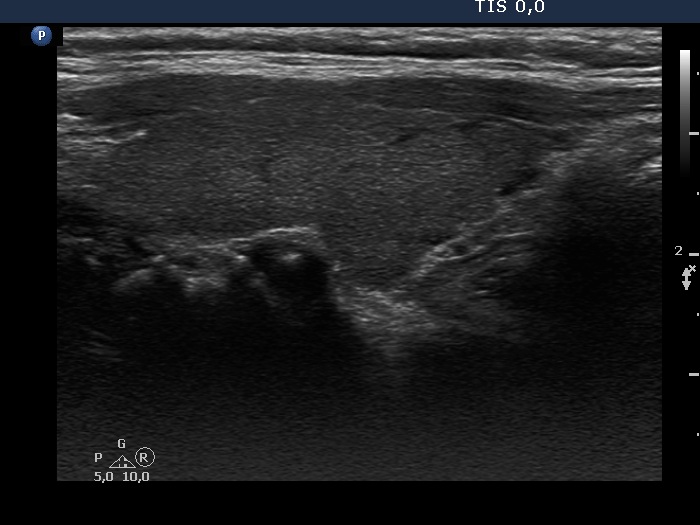

Consecutive patients with the final diagnosis of Hashimoto's thyroiditis - case 53 (101) (ultrasonographic picture 2)

Right lobe, longitudinal view. The small discrete areas make a pseudonodular appearance to the lobe.